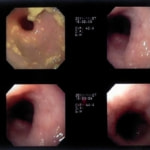

内視鏡下写真

内視鏡検査:肛門付近の直腸全周に、炎症および出血を伴う結節状病変を多数認めた。